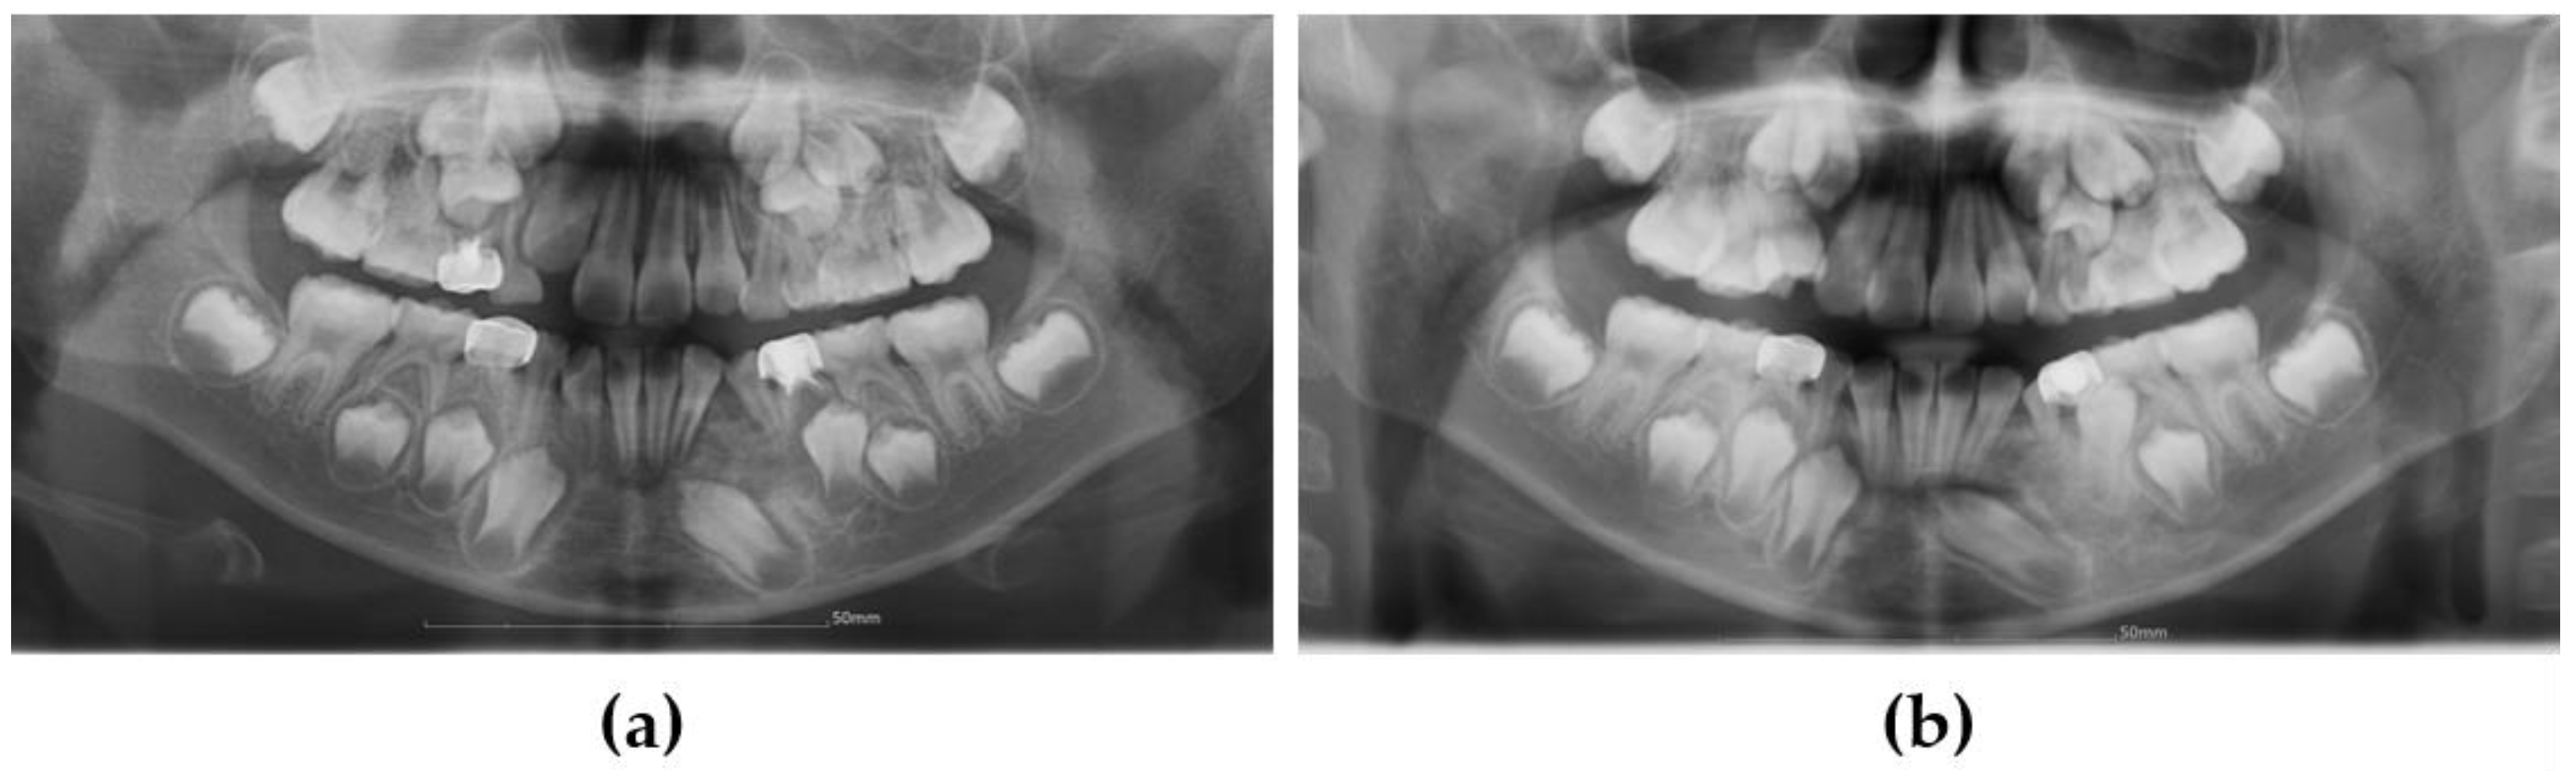

3.1. Case 1

3.2. Case 2